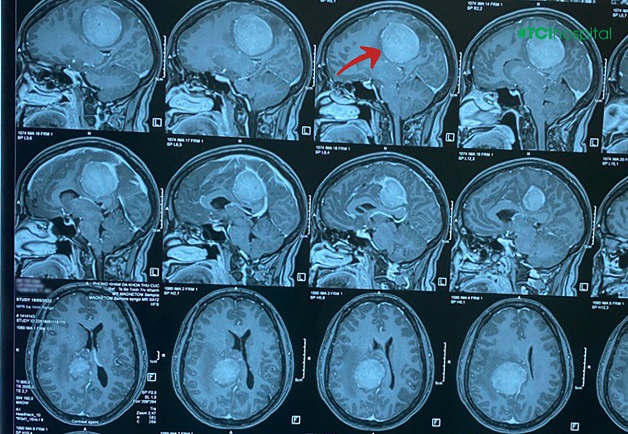

Tai biến mạch máu não là một trong những căn bệnh phổ biến gây ảnh hưởng lớn đến sức khỏe mà rất nhiều người gặp phải đặc biệt là người lớn tuổi. Vì vậy để có cách phòng ngừa căn bệnh này hiệu quả chúng ta cần phải tìm hiểu, nắm rõ về các giai đoạn của bệnh. Bài viết dưới đây là những thông tin cần thiết 8 dấu hiệu tổn thương thần kinh Mời các bạn cùng theo dõi.

Tổn thương thần kinh thường phát triển chậm, việc chẩn đoán đúng không phải lúc nào cũng đơn giản. Dưới đây là những dấu hiệu tổn thương dây thần kinh mà bạn không nên bỏ qua. Tổn thương thần kinh là căn bệnh do nhiều nguyên nhân như lão hóa, thiếu hụt vitamin, phơi nhiễm với độc tố (bao gồm cồn và các thuốc chống ugn thư) và các nhiễm trùng, các bệnh tự miễn như viêm gan C, bệnh bạch hầu, HIV, Epstein-Barr, viêm khớp dạng thấp và hội chứng Guillain-Barré. Khoảng 30% trường hợp đau thần kinh vô căn, nghĩa là không có nguyên nhân.